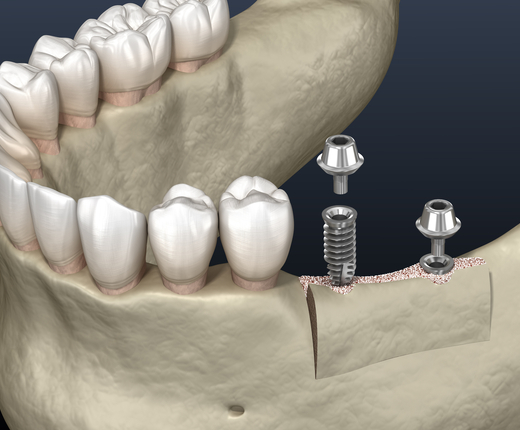

The alveolar ridge is the part of the jawbone that supports the teeth. After a tooth is removed or lost, the bone can shrink, a process called jawbone resorption. If the ridge becomes too thin or uneven, it may not support a dental implant. Ridge augmentation uses bone grafting to restore the natural shape and width of the ridge.

Ridge preservation is a bone graft placed at the time of extraction to maintain the socket's shape. Ridge augmentation is performed later when ridge loss has already occurred and additional rebuilding is needed. Both approaches aim to limit bone loss and prepare for future restorations.

Graft Placement

Bone graft material is placed to rebuild the ridge. A membrane may protect the graft during healing.